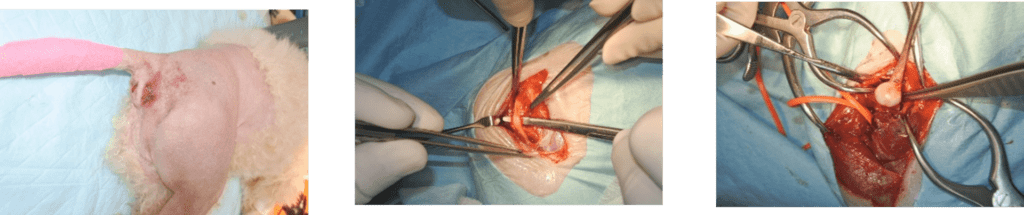

全身麻酔をかけ、手術する足の毛を刈り、皮膚をきれいに消毒します。まず、皮膚を切開し、靱帯などを切らないように股関節を露出し、外れてしまっている股関節(大腿骨頭)を確認します。

次に、骨盤のくぼみ(寛骨臼)に、ドリルで小さな穴を1つあけます。あけた穴に、「トグルピン」という小さな金属の棒(ボタンの裏の留め具のようなもの)が結ばれた、非常に丈夫な特殊な糸を通します。穴を通って骨盤の内側に出てきたトグルピンを、糸を引っ張ることで90度回転させます。すると、トグルピンが骨の内壁にしっかりと引っかかり、糸が抜けなくなります。

続いて、太ももの骨(大腿骨)の、関節に近い部分にもドリルで穴をあけます。骨盤側に固定された丈夫な糸を、太ももの骨にあけたトンネルに通します。そして、関節がグラグラしないように適切な強さで糸を引っ張りながら、しっかりと結びつけます。これで、骨盤と太ももの骨が丈夫な糸(人工の靭帯)で繋がれ、関節が安定し、脱臼しなくなります。関節が安定していることを確認したら、切開した部分をきれいに縫い合わせて手術は終了です。